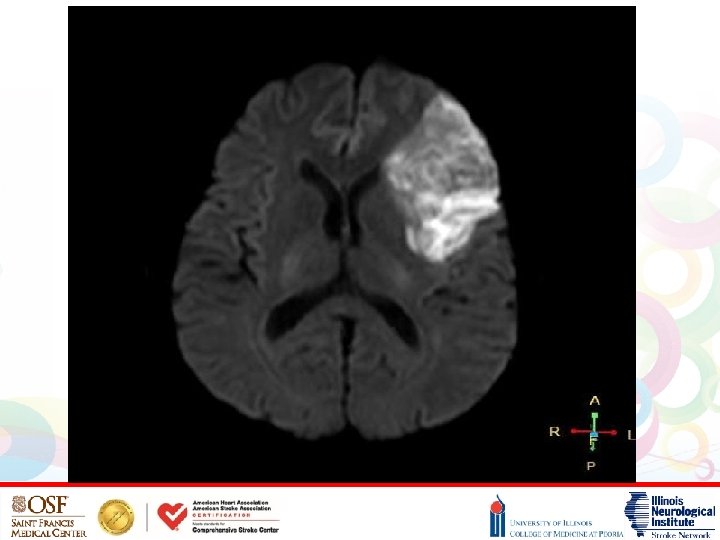

HYPERTENSIVE INTRACEREBRAL HEMORRHAGE • HTN is also the most common cause of intracerebral hemorrhages • Patho-physiologically, long-standing poorly controlled HTN leads to formation of microaneurysms of perforating arteries (Charcot-Bouchard aneurysms) • These small penetrating arteries can leak or rupture leading to hemorrhagic strokes • The most common locations for hypertensive hemorrhages include the basal ganglia (particularly the putamen), thalamus, pons, and cerebellum (Di. Muzio, Radiopedia, 2017)